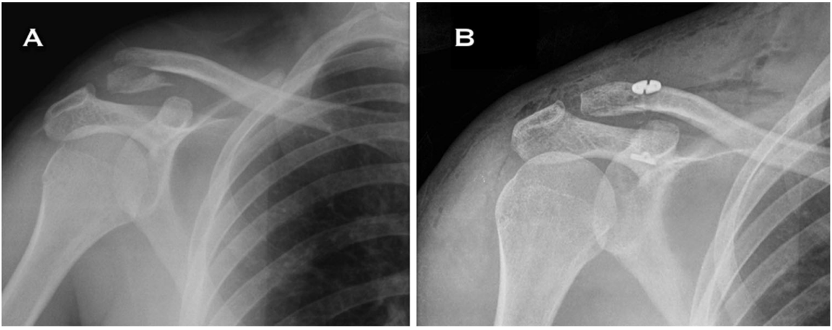

对于不稳定性骨折,手术治疗效果优于保守治疗。下面以图片的形式展示不同的固定方法。

锁骨远端锁定钢板固定

铆钉结合张力带克氏针固定

铆钉结合张力带克氏针固定后再次骨折,但转化为中段骨折,予以钢板固定

关节镜下袢钢板固定结合缝线固定骨折

桡骨远端锁定钢板用于锁骨远端骨折

钩钢板用于锁骨远端骨折固定